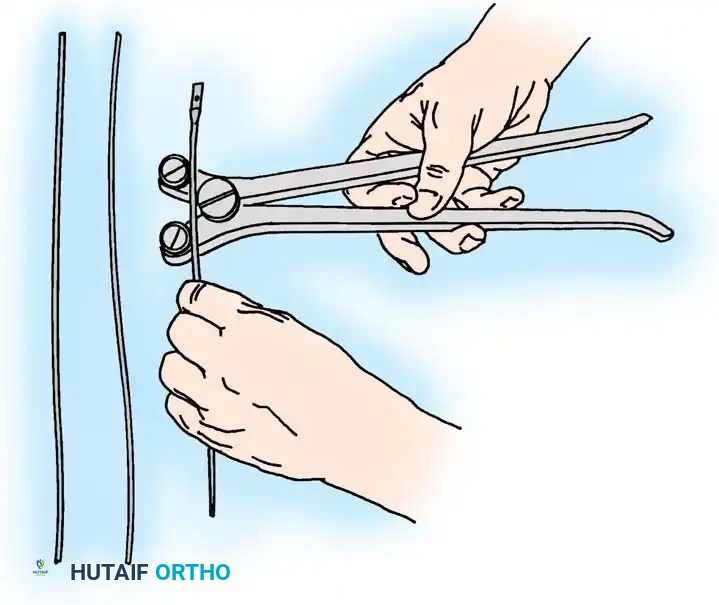

🔪 Surgical Technique: Tension Band Wiring

- Drill Hole: Drill a transverse hole from side to side in the distal ulnar fragment, approximately 2 to 3 cm distal to the fracture line. Ensure the hole is deep enough to avoid cutting through the posterior cortex.

- Wire Passage: Pass an 18-gauge (1.2 mm) stainless steel wire through the drill hole.

- Proximal Purchase: Pass the wire beneath the aponeurosis of the triceps muscle, directly adjacent to the bone, and around the tip of the olecranon. Alternatively, a transverse drill hole can be made in the proximal fragment if it is large enough.

- Figure-of-Eight: Carry one end of the wire obliquely across the posterior aspect of the fracture to the opposite side. Cross the other end over it to create a figure-of-eight configuration.

- Reduction and Compression: While an assistant grasps the proximal olecranon fragment with a large towel clip and exerts distal traction to anatomically reduce the fracture, twist the wire loop tightly.

Fig. 54-54 Internal fixation of olecranon with tension band wire loop. Wire passed through hole drilled in distal fragment and through triceps aponeurosis adjacent to bone. Figure-of-eight loop adds stability to fracture and prevents distraction and posterior bowing.

🔪 Surgical Technique: K-Wire and Tension Band (AO Technique)

- Reduction: Anatomically reduce the fragments and hold them temporarily with a reduction clamp.

- K-Wire Insertion: Introduce two parallel K-wires longitudinally from the tip of the olecranon across the fracture site. Direct them slightly anteriorly so they engage the anterior ulnar cortex distal to the coronoid process.

- Wire Loop: Pass an 18-gauge wire through a transverse drill hole in the distal fragment. Cross the wire in a figure-of-eight fashion over the posterior surface.

- Proximal Capture: Pass the wire around the protruding proximal ends of the K-wires.

- Double Twist: Weber and Vasey suggest twisting both limbs of the figure-of-eight loop. This double-twist modification ensures uniform compression across the fracture site.

- Securing K-wires: Bend the proximal ends of the K-wires 180 degrees, cut them short, and tap the bent ends deep into the triceps insertion and proximal bone to prevent symptomatic hardware prominence and migration.

Fig. 54-56 A and B, Transverse olecranon fracture repaired with Kirschner wires and tension band technique. C, Double twist modification of wiring suggested by Weber and Vasey.